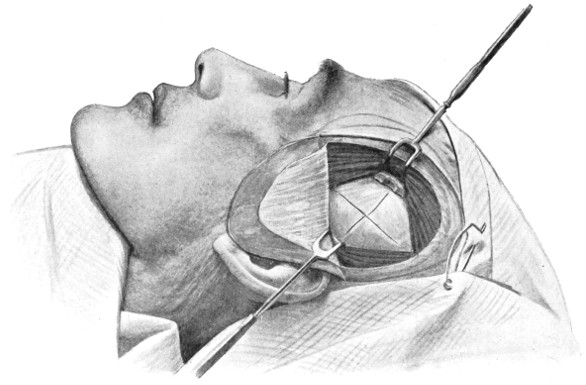

Fig. 17. First Stage in the Formation of an Osteoplastic Flap. Gigli’s saw, protected from the dura mater by the special director, passing between the two trephine-holes. For further description, see text.

Between these two trephine-holes the dura mater is separated from the bone and the special director introduced, entering at the one hole, emerging at the other, and lying throughout between the dura and the bone. The saw is now passed along the groove of the director, the handles affixed, and the bone intervening between the two trephine-holes divided, not straight out to the surface, but bevelled or cut in such an oblique manner that the bone-flap, when replaced, rests on a ledge (see Figs. 17-19). The sawing process[26] generates considerable heat, and the assistant should be instructed to keep up irrigation with saline solution or sterilized water. The sawing is carried out by steady side-to-side traction, without jerks; if the saw breaks, the special handle may be attached, thus obviating the necessity of introducing a new saw.